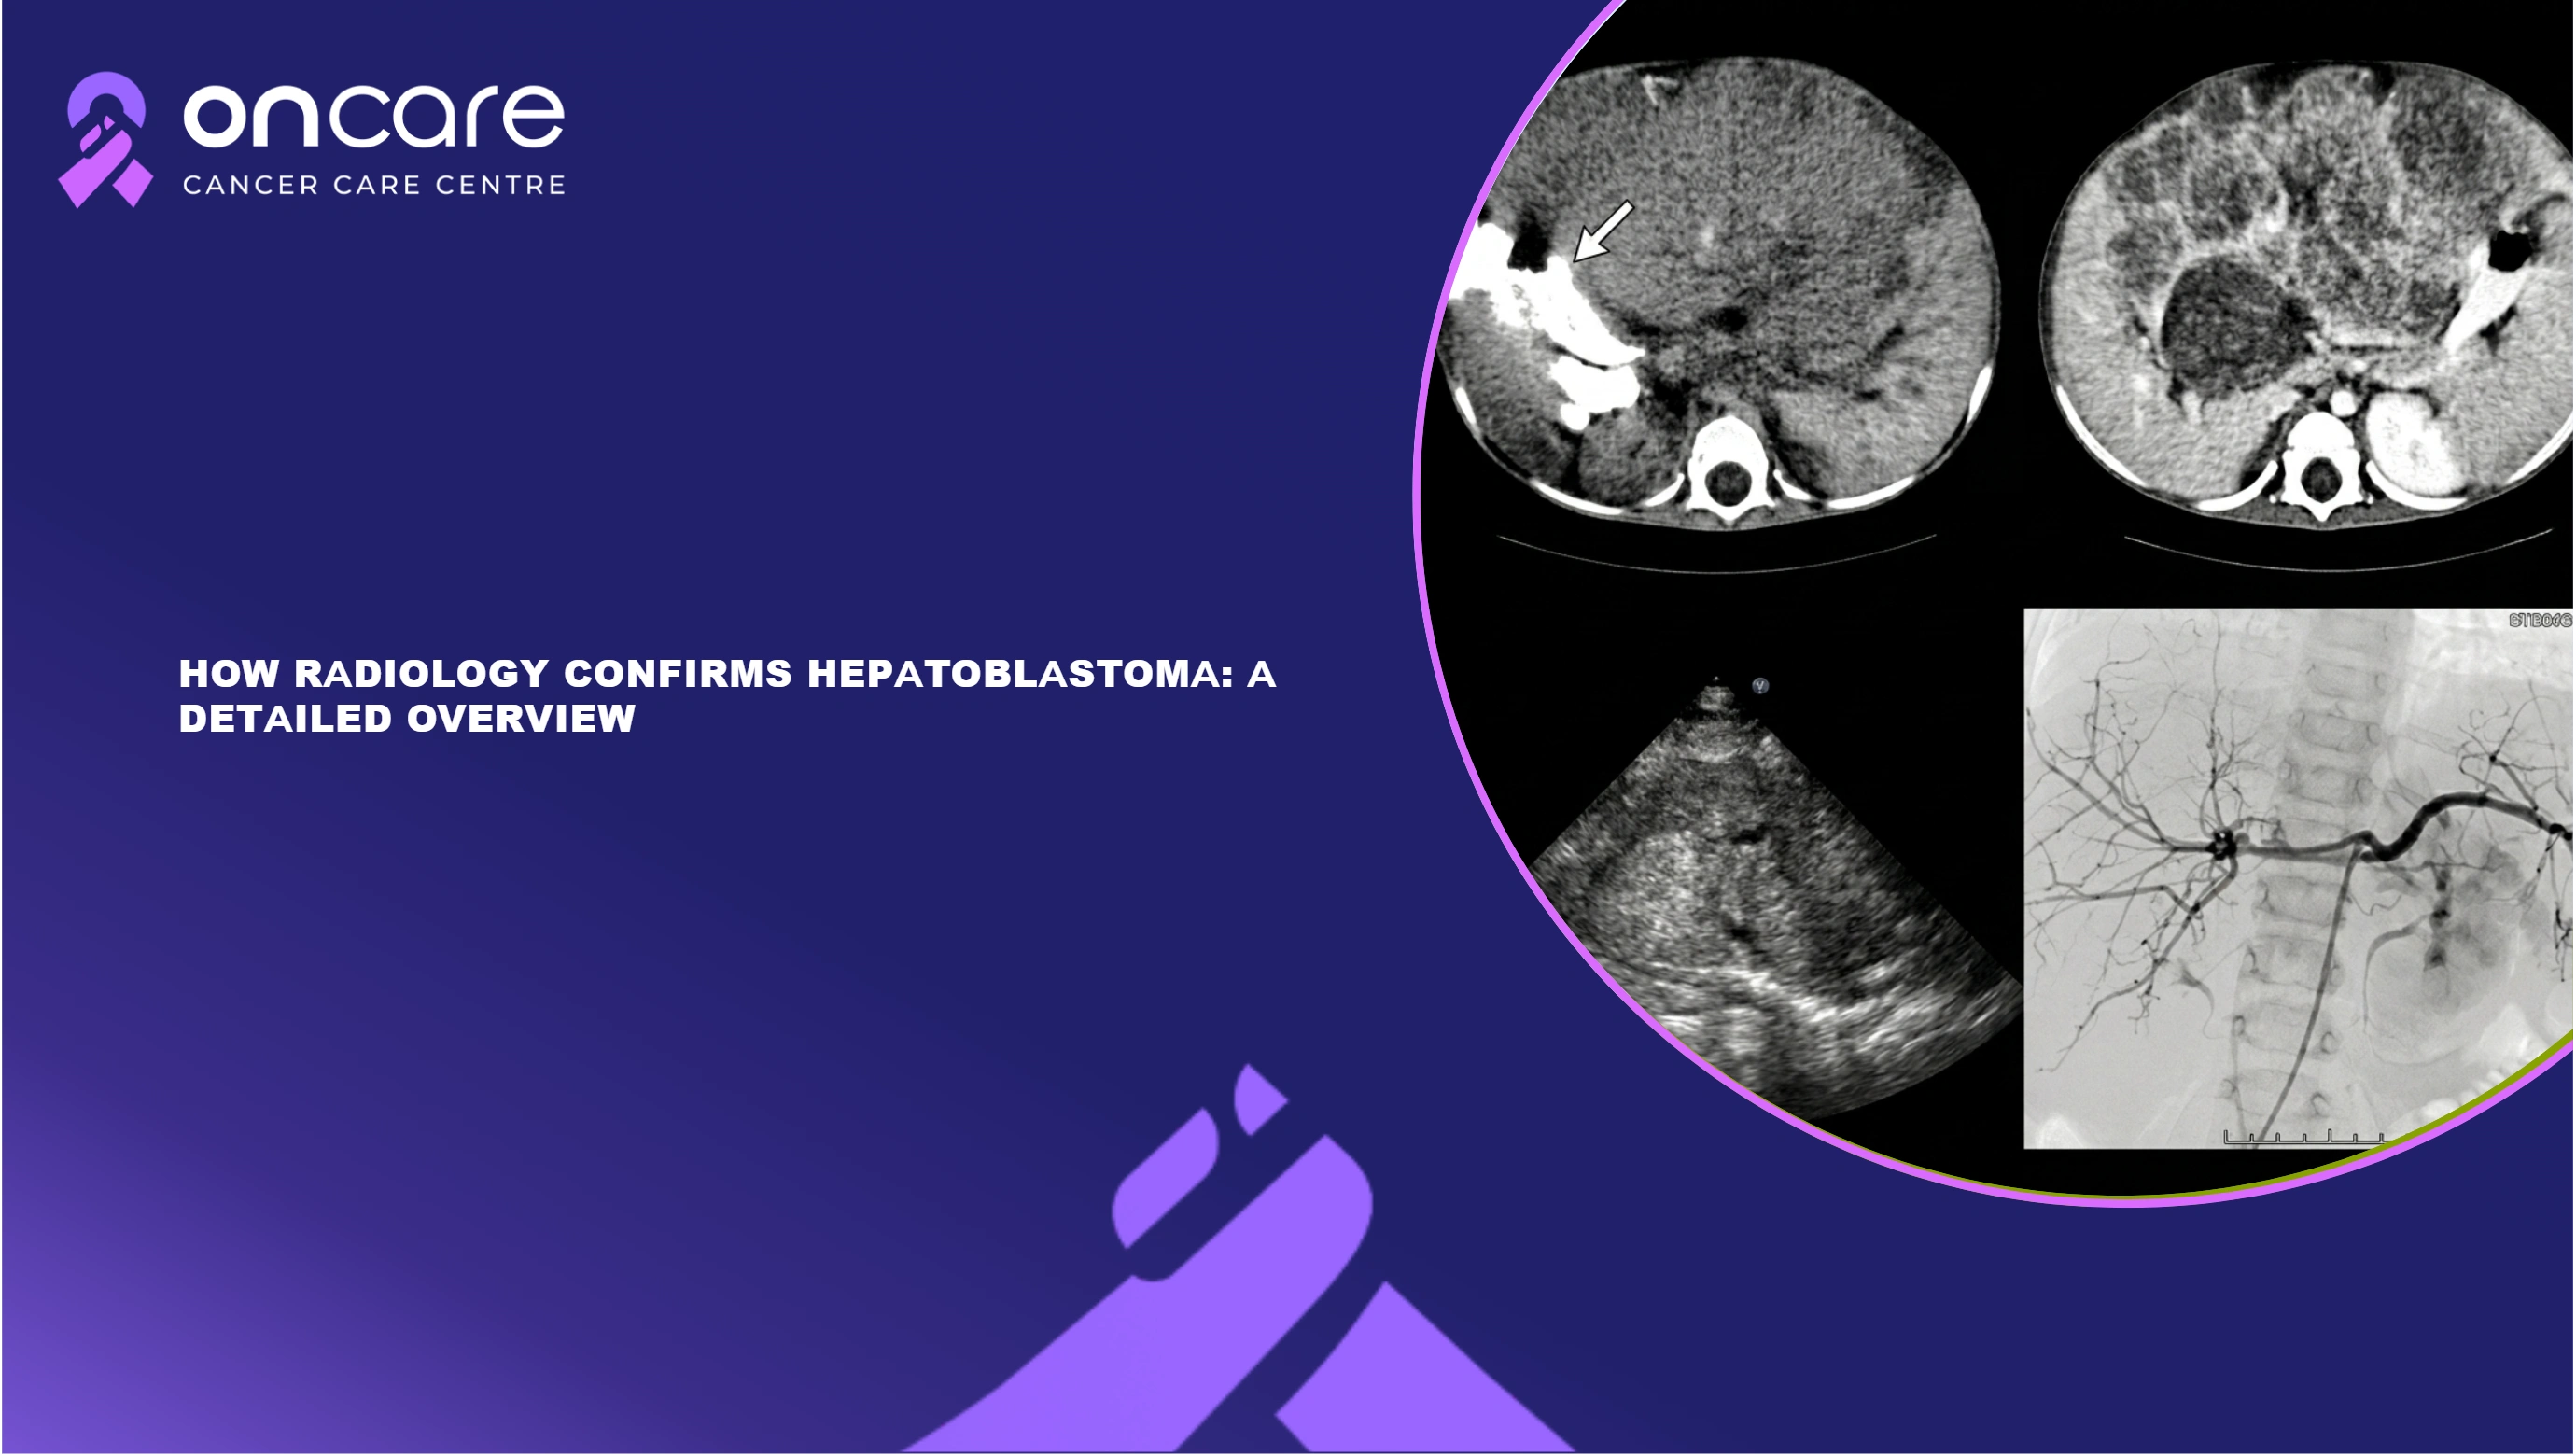

When doctors think a child could have a liver disease, they usually undergo an ultrasound first. It is safe, painless, and doesn't use any radiation. In hepatoblastoma radiology, ultrasonography is used to find strange growths in the liver. It can tell you whether there is a mass and give you a sense of what it is like. It might not give all the information, but it's a good place to start when trying to figure out what's wrong through hepatoblastoma radiology.

A CT scan shows more detail than an ultrasound. It makes cross-sectional photographs of the body using X-rays. CT scans help doctors see the extent of the tumor and whether it has spread to neighboring organs in hepatoblastoma radiology. It is very helpful to know this information when figuring out what stage the cancer is in and arranging surgery or other therapies using hepatoblastoma radiology.

MRI is another great imaging method that radiologists employ to look at hepatoblastoma. Instead of radiation, it employs magnetic fields to make precise pictures. MRI is great at displaying soft tissues clearly. It can let doctors see the liver and blood arteries better, which helps them figure out how the tumor is affecting neighboring structures. This makes it safer to plan treatment with the help of hepatoblastoma radiology.